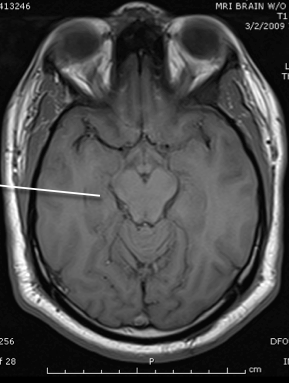

tegmentum and tectum of midbrain

third ventricle

hypothalamus